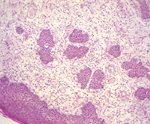

腫瘤物由數個軟組織團塊所形成,觸感硬,白色,長約 2.5 公分 × 寬約 l.5 公分,表面有出血及潰瘍現象(圖一)。 三、 組織病變: